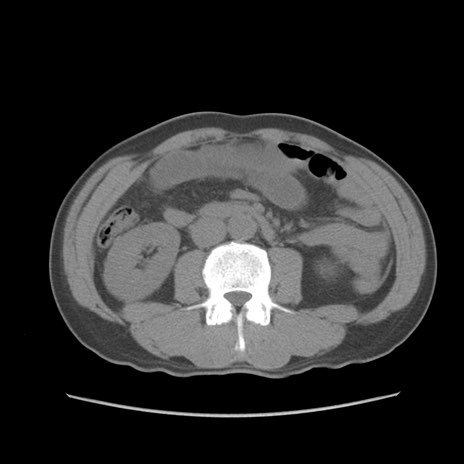

症例56 CT(横断像)

脂肪ウインドウ